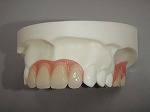

◆総入れ歯

当院の総入れ歯では、リンガライズド・オクルージョンという特別な噛み合わせで製作しております。この噛み合わせの特徴は、小さな力で食品を破砕することが可能となり、ハグキが吸収して食事中、入れ歯の安定が悪い方にお勧めです。